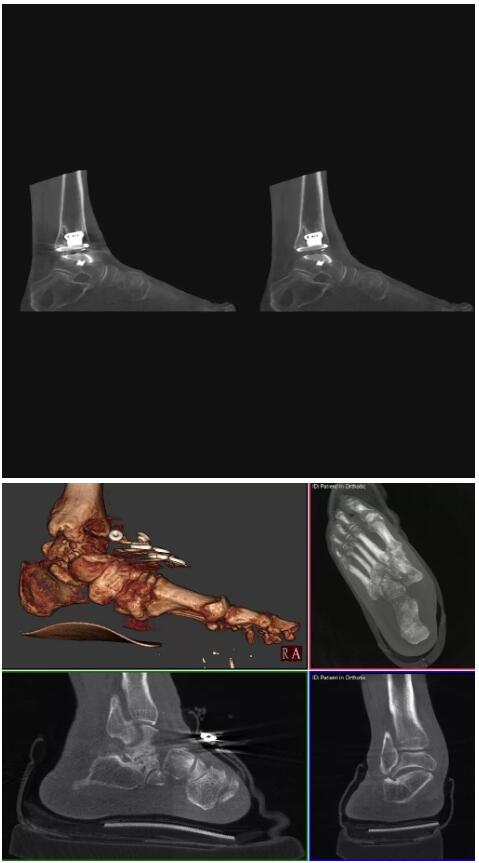

比如上面這款專用于足部和踝部掃查的CT成像系統(tǒng),患者在進(jìn)行CT掃查時只需要站在上面即可,雙腳站或者單腳站都可以,當(dāng)然,如果患者不是那么方便站著做完CT掃查,也可坐在上面。

這款CT掃查系統(tǒng)自帶屏蔽裝置,它的體積非常小,僅需要極小的空間即可,并不像常規(guī)CT那樣需要一間單獨(dú)的檢查室。此外,這種CT掃查的速度非???,僅需30秒左右可以完成檢查,輻射劑量相對常規(guī)的CT要少許多,尤其適合醫(yī)院的骨科使用。

而患者站著做足部或者踝部做CT檢查還有個好處是,可以檢查患者在負(fù)重的情況下,骨關(guān)節(jié)的真實(shí)情況,而躺著做CT掃查時未必能看出來。負(fù)重CT掃查特別是對于受傷的運(yùn)動員或者舞蹈員來說意義更大,能夠更準(zhǔn)確地評估傷情,幫助他們盡早復(fù)原。

以上介紹的CT均來自國外同一家公司,這些CT均配置了可視化軟件,可以進(jìn)行切片、3D重建以及大型CT附帶的所有典型的操作功能。

以下是這些“特立獨(dú)行”的CT所拍出來的圖像: